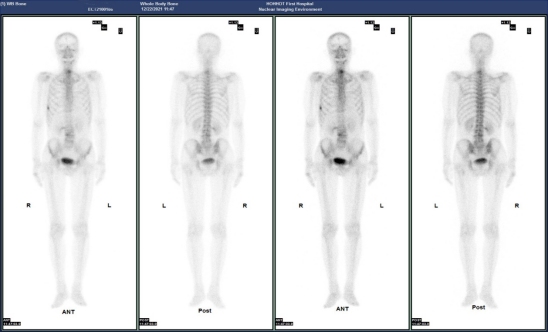

(病例二)患者,男,63岁,患者因胸憋气短、间断咳嗽咳痰就诊。门诊CT示:双肺底感染;右肺上叶占位性病变。患者今年4月份提重物时感右侧胸部拉伤,后疼痛数日。MIP图示:C6/C7椎体吻合面、右侧第7侧肋小片状放射性摄取增高,SPECT/CT示:右侧第7侧肋骨质不连续,可见骨痂形成。C6/C7椎体吻合面可见唇样骨质增生,椎体周围软组织无明显肿胀。结合病史,考虑右侧第7侧肋骨折愈合期;C6/C7椎体吻合面终板炎。